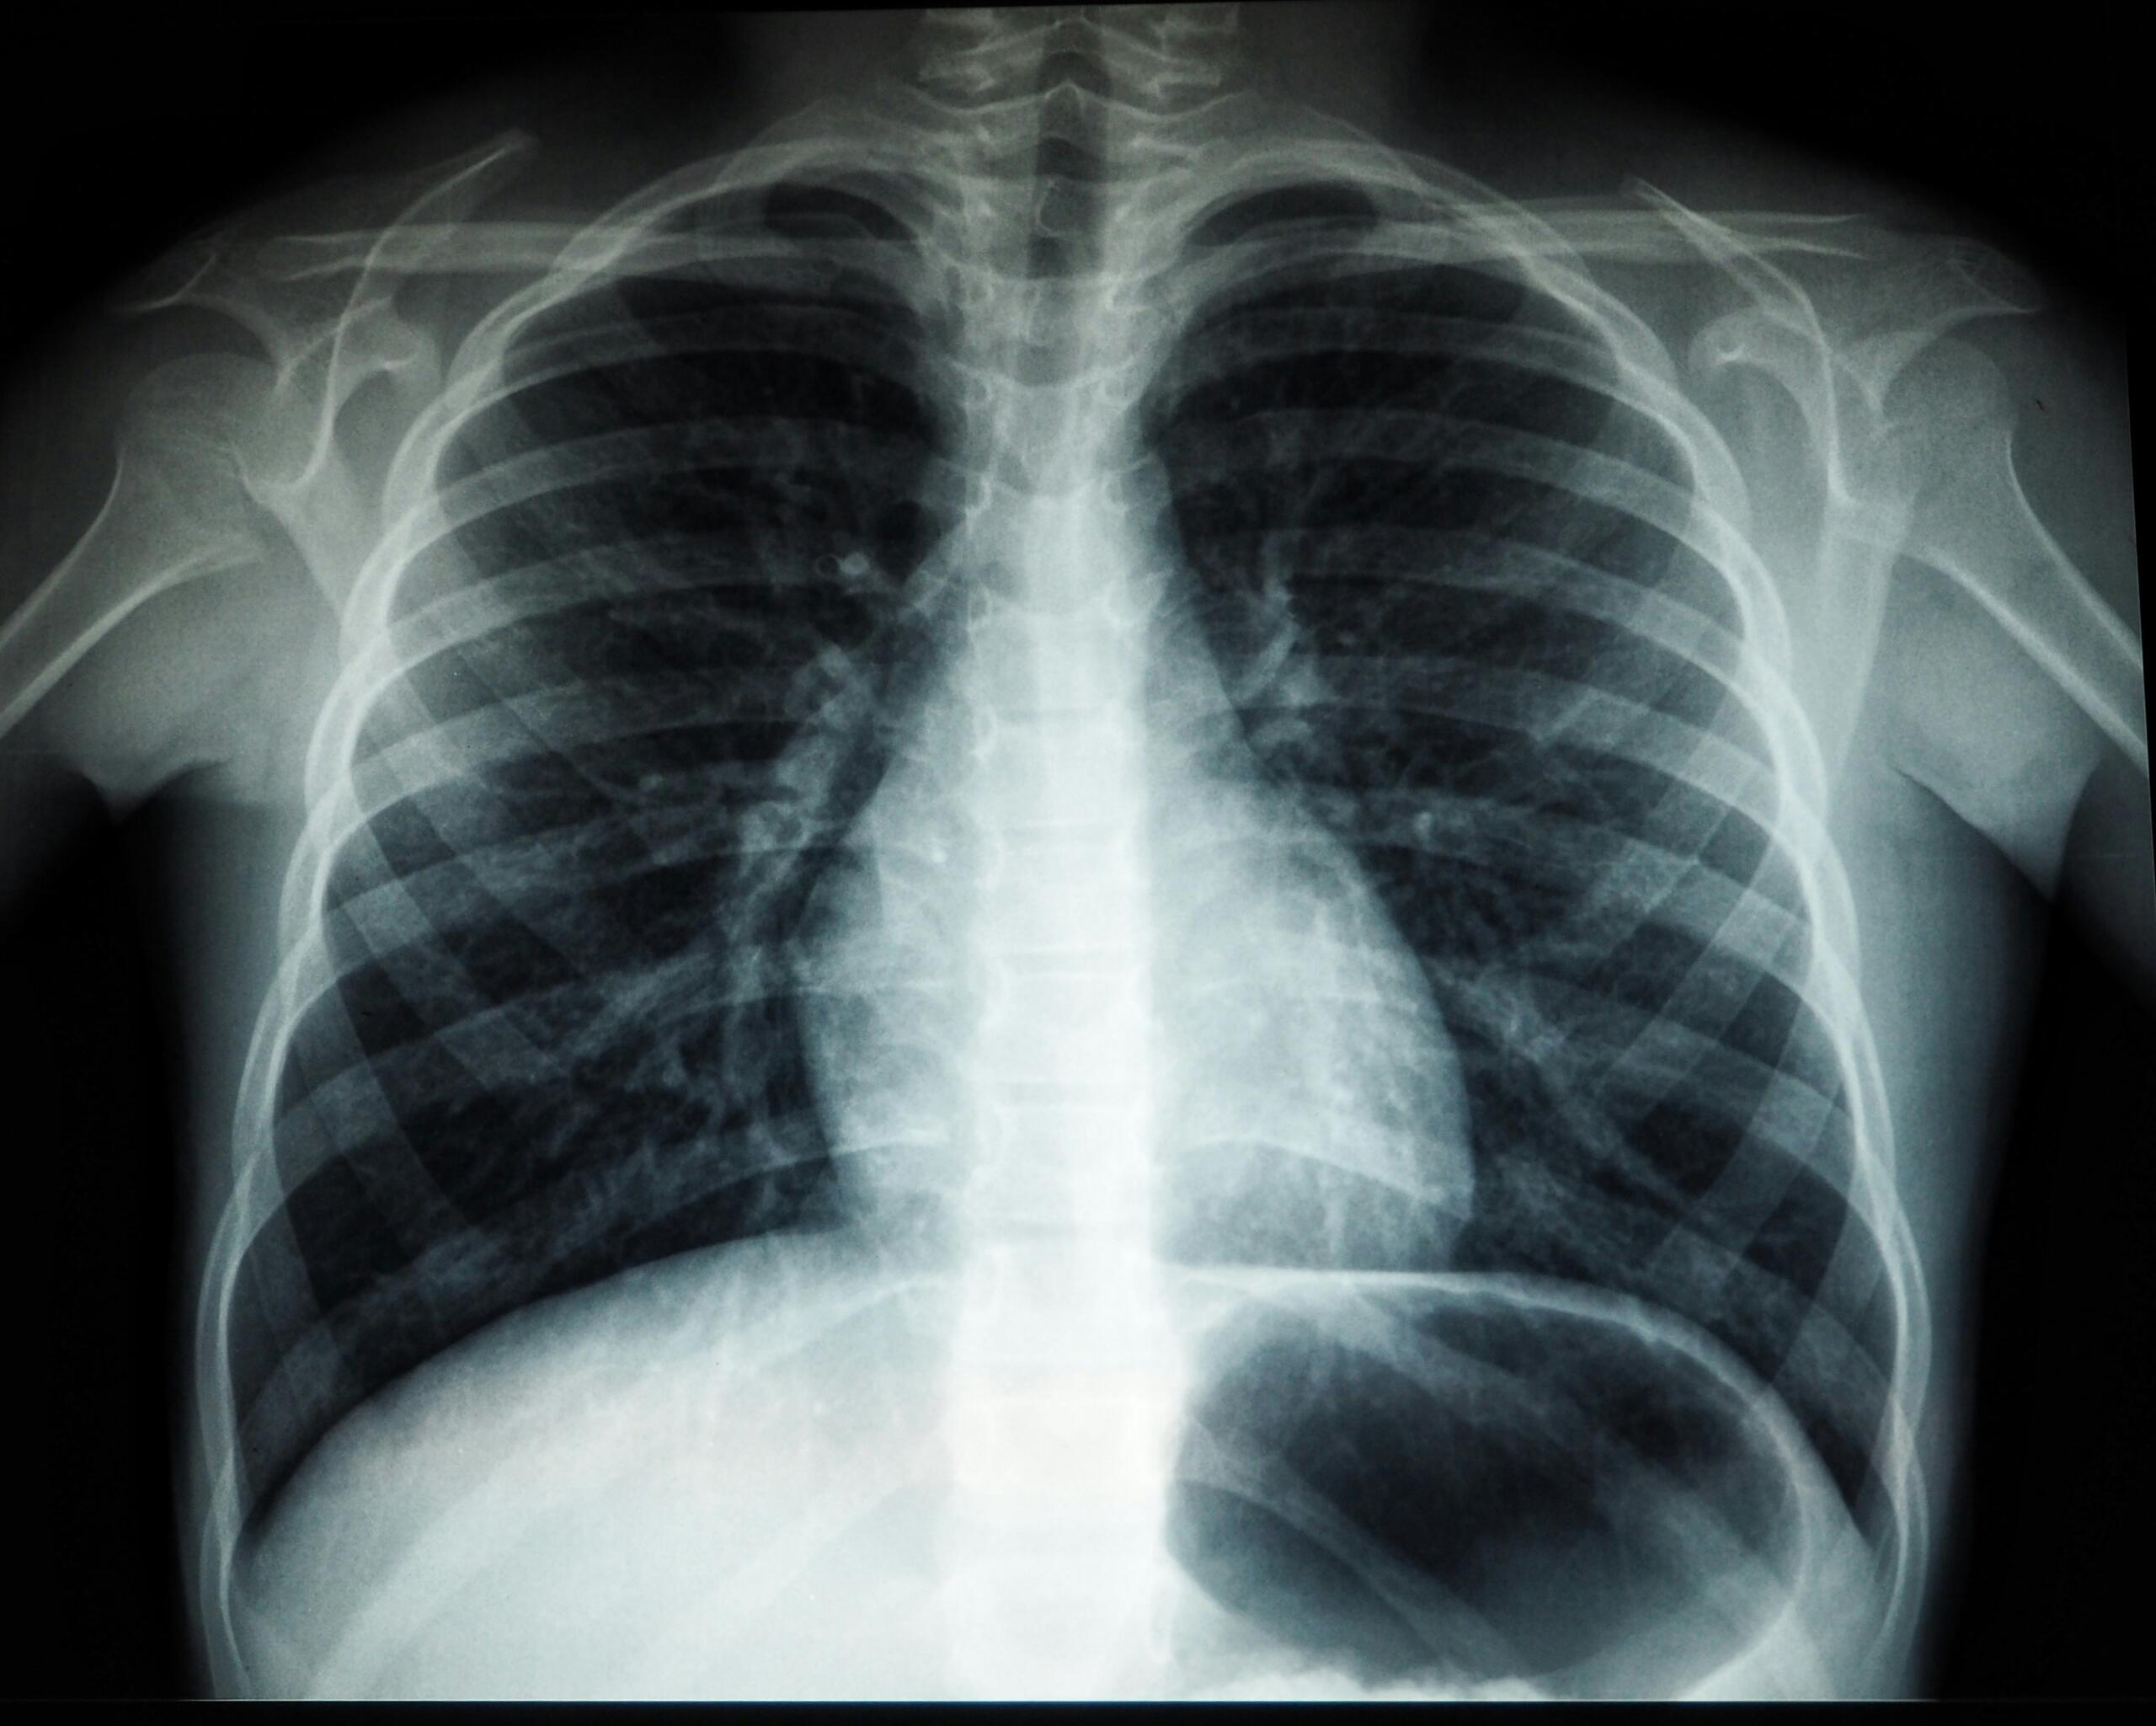

Συνήθως, ο καρκίνος εντοπίζεται μέσω απεικονιστικών εξετάσεων, όπως ακτινογραφίες, μαστογραφίες ή μαγνητικές τομογραφίες. Οι δεκαετίες συσσωρευμένων απεικονιστικών δεδομένων έχουν επιτρέψει την εκπαίδευση της τεχνητής νοημοσύνης στον εντοπισμό όγκων και κυτταρικών αλλοιώσεων με μεγάλη ακρίβεια. Η πρόοδος αυτή δεν είναι μεμονωμένη, αλλά εντάσσεται σε ένα ευρύτερο σύνολο εξελίξεων που χαρακτηρίζουν τα πιο σημαντικά ιατρικά επιτεύγματα των τελευταίων ετών.

Ακόμη και σε αυτό το αρχικό στάδιο, τα αποτελέσματα είναι ιδιαίτερα ενθαρρυντικά. Σύμφωνα με δημοσίευση στο επιστημονικό περιοδικό The Lancet, η απόδοση της AI στην ιατρική διάγνωση είναι ισοδύναμη με εκείνη των επαγγελματιών υγείας.

Η έγκαιρη ανίχνευση του καρκίνου είναι καθοριστική για την πορεία της νόσου. Όσο νωρίτερα εντοπιστεί ένας όγκος, τόσο περισσότερες επιλογές θεραπείας έχει ο ασθενής. Η τεχνητή νοημοσύνη μπορεί να αναγνωρίσει μοτίβα που δεν είναι άμεσα ορατά, ενισχύοντας σημαντικά την ακρίβεια στην ιατρική διάγνωση.